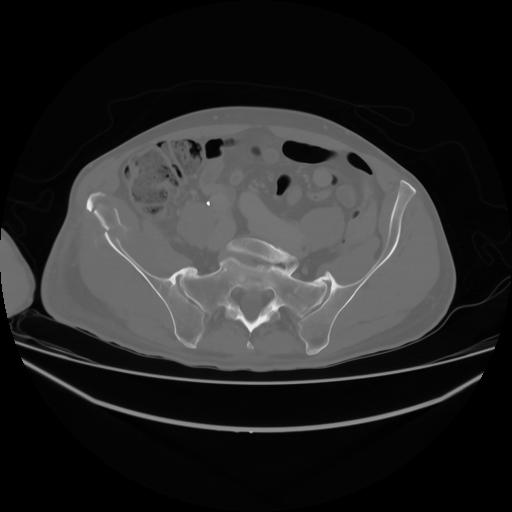

4 CUERPO,CE,Axial,3.0,CUERPO,,